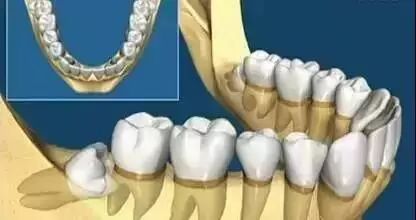

▲智齿的各种生长状态

看看上图这些智齿的生长位置,真是千奇百怪。你觉得那颗最好拔?智齿但一旦生长位置出现了偏差,那就得科普另外一个词,阻生智齿。

上面说过,小小的智齿也有很多分类,生长的姿势也不尽相同,这也就造成了想要拔除它的难易程度不一样。

又或者~他长成了下面任何一款: